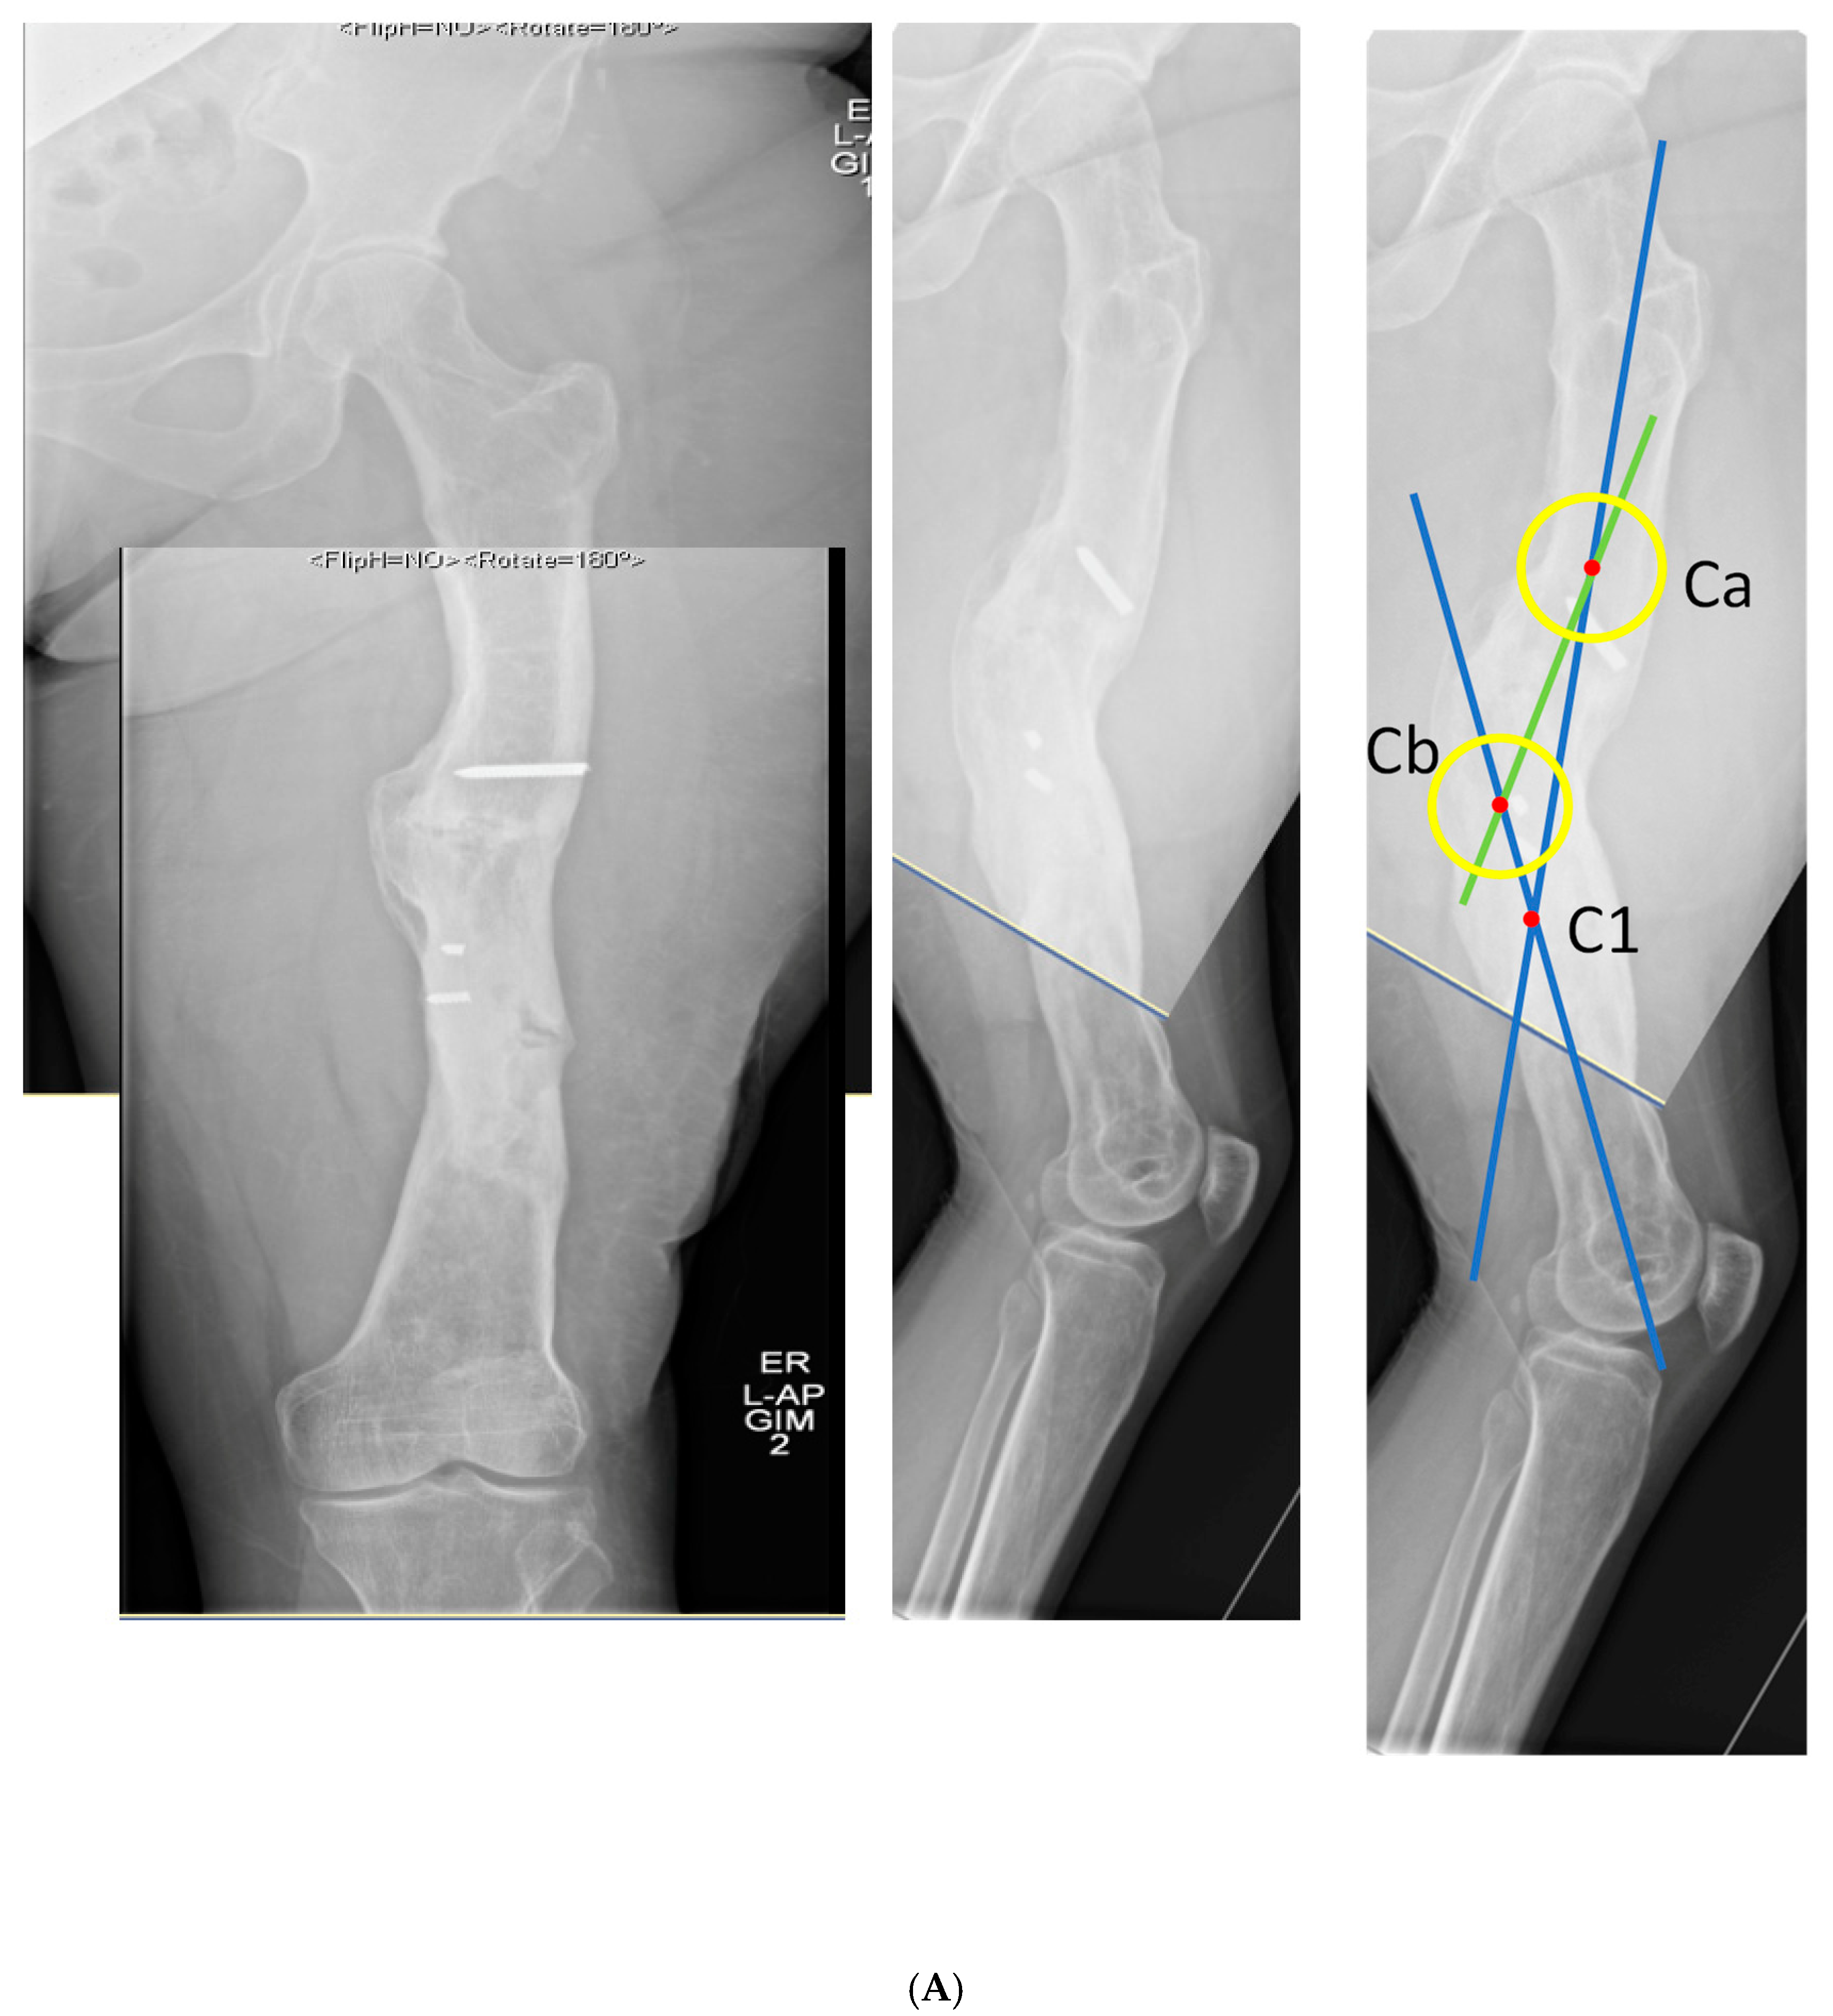

3.1. Case 1-Multifocal Correction with Intramedullary Nail: Femur

The patient is a middle-aged female with no comorbidities other than obesity who presented 26 years after an open diaphyseal femur fracture with more than 10 surgeries for attempted union and eradication of infection. The patient presented with complaints of pain at the mid-femur and knee, a chronically draining sinus of the lateral thigh, and concern for a 2-cm-short left leg. No rotational deformity is found. The limb clinically appears normal in the coronal plane. The patient has a 15-degree knee contracture. X-rays reveal a malunion of the left femur with bone sequestrum and retained hardware (Figure 6A). A metabolic workup, including the vitamin D level, is normal. The CT scan characterizes the pathological bone, allowing for precise localization of the sequestrum (Figure 6B). A deformity analysis reveals a primarily sagittal plane deformity with limb shortening. The traditional CORA analysis demonstrates translation with angulation, as demonstrated by a CORA located outside of the deformity. With the expected multiple stages, a double-level focal dome was chosen over clamshell, allowing stable weight-bearing while not requiring an extended femoral osteotomy to heal through pathological bone. The other consideration for this patient was radical en bloc resection of the diseased bone, with either bone transport or secondary reconstruction with a compressed allograft intercalary segment. This concept was reserved as the option if the current plan failed.

Figure 6.

(A) Middle-aged female with 26 years of an infected draining sinus of the left femur with malunion and shortening. The intersection of the two blue lines represents the CORA of the proximal and distal diaphyseal segments (C1). A CORA outside of the deformity reveals translation in addition to angulation. The intersection of the green line with each blue line represents an alternative where the central deformed segment is also incorporated into the analysis, revealing two CORA center points for double-level osteotomy (Ca and Cb). (B) The patient was found to have retained hardware and a bone sequestrum. Sequestrectomy with antibiotic local delivery via a coated intramedullary nail with concomitant systemic antibiotics would promote infection eradication. (C) The patient underwent double-level focal dome osteotomy at the time of initial debridement. The patient had two sequential debridements over 10 days. Stabilization using an interlocking antibiotic coated nail was placed during the final debridement. (D) Five months postoperative, where the distal osteotomy was autogenous-grafted from the patient’s contralateral femur due to the persistent osteotomy gap. Chronic suppression oral antibiotics were recommended; patient voluntarily stopped antibiotics at 24 months. (E) Three-year final follow-up with normal serological markers and no sign of recurrence. Osteotomies healed. Soft tissue healed.

The patient underwent double osteotomy using focal dome osteotomy at Ca and Cb (Figure 6C), with retained hardware removal and resection of the infected sequestrum and surrounding diseased bone. A direct lateral approach to the thigh was used, and the diseased soft tissue track was excised and analyzed by pathology. A temporary nail was inserted and replaced with an antibiotic-coated interlocking nail ten days later with a planned second debridement. The nail was compressed using the internal compression instrumentation associated with the nail. A gap in the distal osteotomy persisted despite attempted removal of the nail and re-reaming with enlarging flexible reamers. This gap was accepted with intent to revisit if bone healing did not progress. The surgical soft tissue approach healed without incident. At five months postoperative, with nonunion of the distal osteotomy at the gap, the patient underwent autograft using contralateral femur reamer–irrigator–aspirator harvesting (Figure 6D). Cultures at the grafting procedure were negative.

The patient progressed to pain-free union at both osteotomies with no recurrence of her infection over three years after osteotomy (Figure 6E).